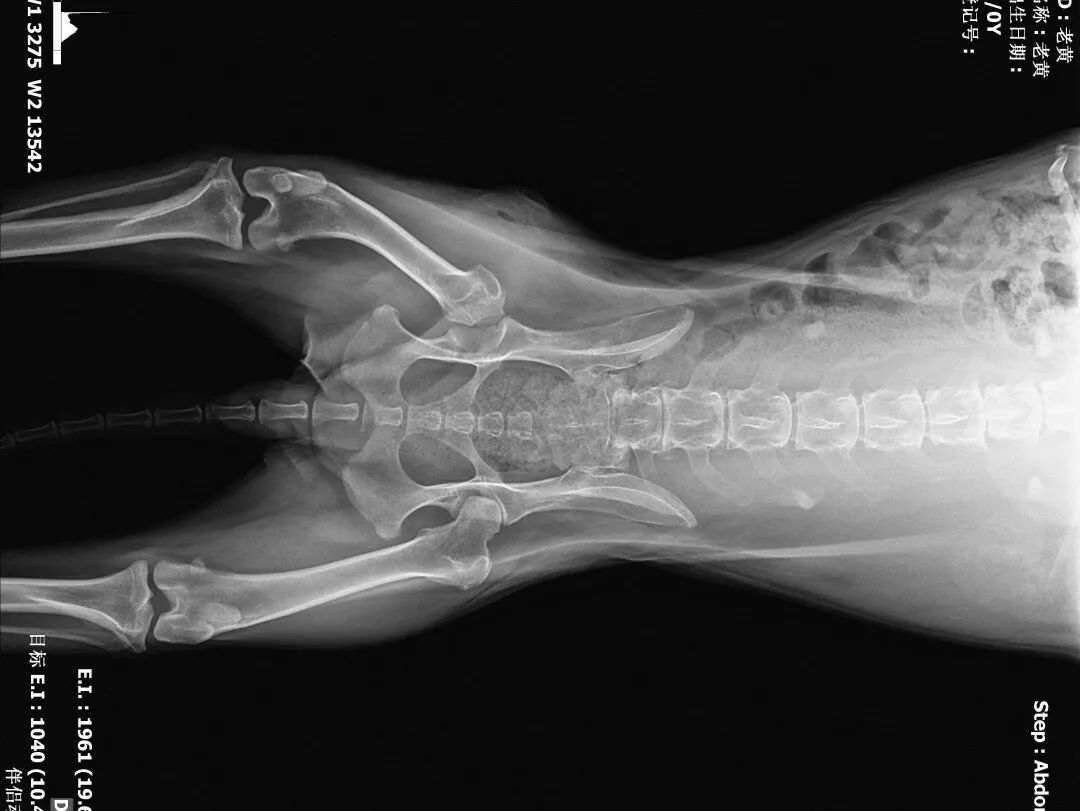

2、血常规、生化、凝血、DR(正侧)

动物拍片腹部怎么摆【病例分享】犬-外科-股骨头切除术_https://www.jmylbn.com_新闻资讯_第5张

术后正位片

动物拍片腹部怎么摆【病例分享】犬-外科-股骨头切除术_https://www.jmylbn.com_新闻资讯_第30张